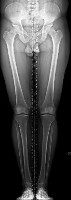

Question 30:

A 2-year-old girl is brought to the pediatric orthopedic clinic by her parents due to worsening bilateral 'bowlegs.' Radiographs reveal a metaphyseal-diaphyseal angle of 18 degrees on the right and 19 degrees on the left, along with medial physeal beaking. She is diagnosed with infantile Blount disease (tibia vara). What is the most appropriate initial management?

Correct Answer: Knee-ankle-foot orthoses (KAFOs)

Explanation:

In infantile Blount disease, a metaphyseal-diaphyseal angle (MDA) greater than 16 degrees predicts progression of the deformity, distinguishing it from physiologic bowing. For children under the age of 3 with Langenskiöld Stage I or II and an MDA > 16 degrees, bracing with a knee-ankle-foot orthosis (KAFO) is the recommended initial management. Surgical intervention (osteotomy or guided growth) is indicated if bracing fails, or typically if the child is over 3-4 years old with advanced stages.